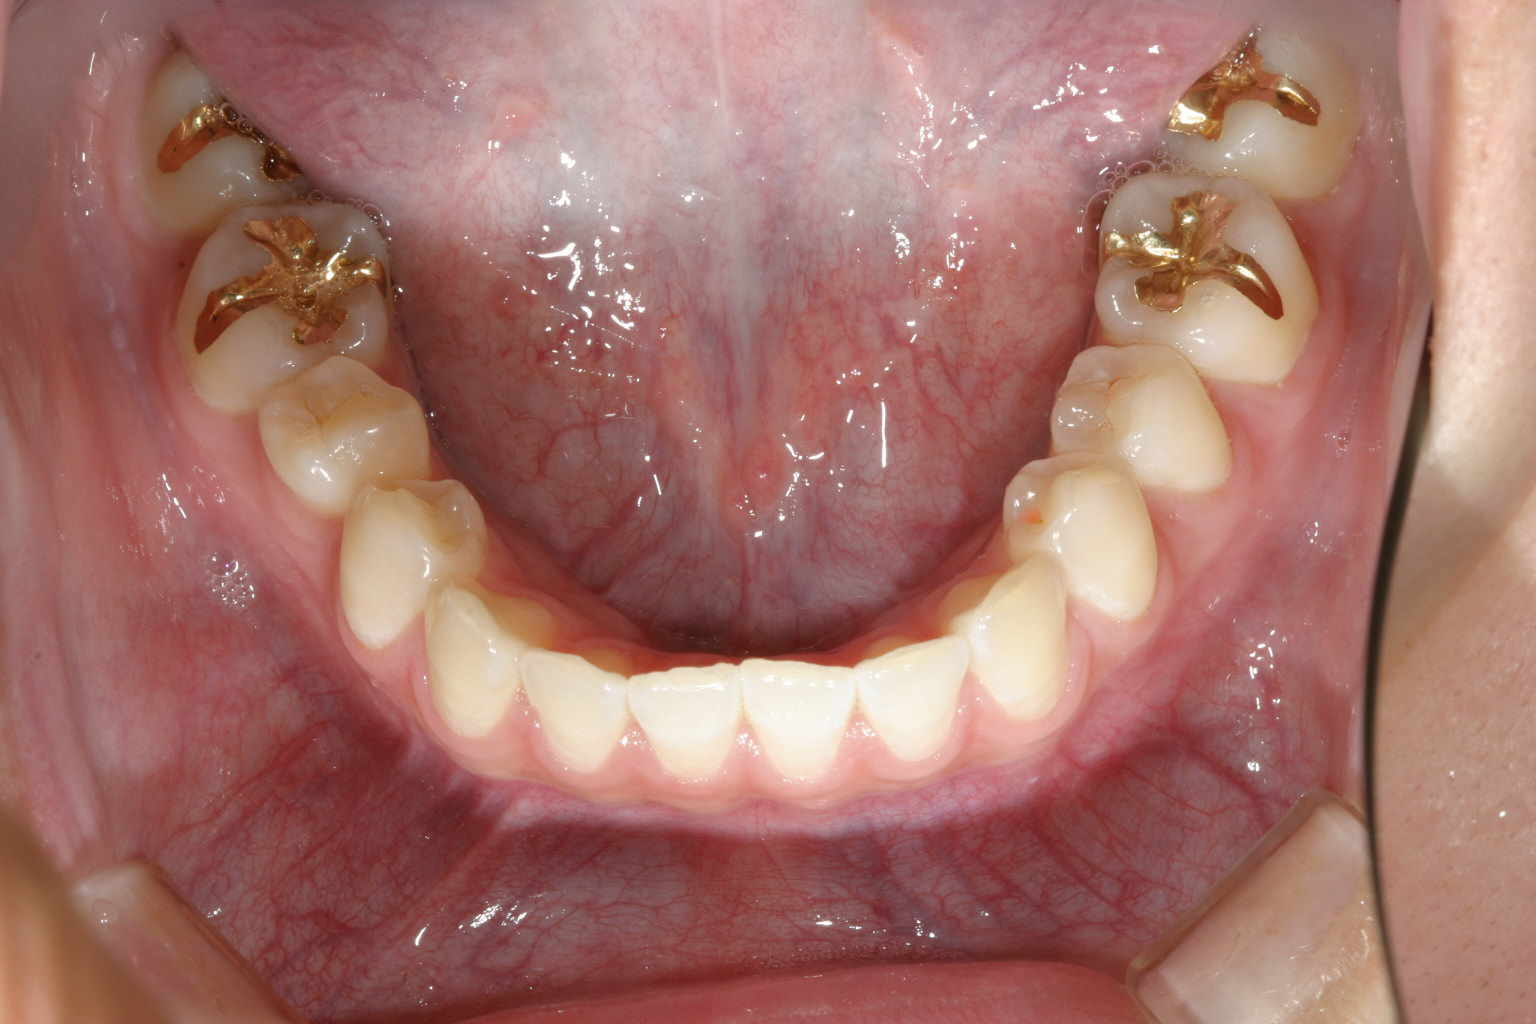

下顎は一見綺麗に見えるのですが右の奥から3本目を見てください。 歯が90°回転しているのが見受けられます。 こういった歯をインビザライン単独で治療するにはかなり難易度が高く治療に相当の期間がかかり 結果として上手く戻らない事が多いです。 その為今回は部分ワイヤーを併用しました。

マルチループワイヤーを用いて右奥から3番目の小臼歯が上手く回転し終わりました。

回転途中の写真です。